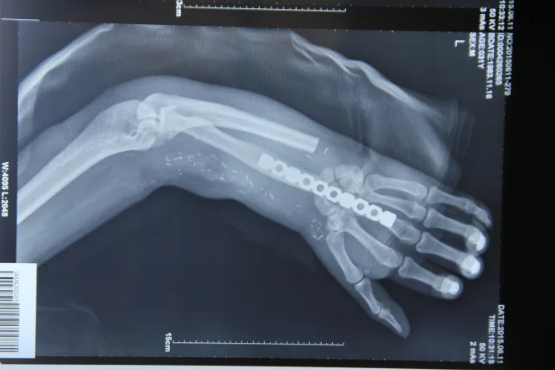

Thay vào đó, họ đã ghép bàn tay vào bắp chân phải của Zhou và kết nối nó với các mạch máu ở vùng đó để duy trì sự sống cho các mô. Cuộc phẫu thuật này là một cuộc chạy đua với thời gian để khôi phục nguồn cung cấp máu cho bàn tay bị rời ra.

Sau khoảng một tháng, khi các mạch máu và gân ở cánh tay của Zhou đã lành lại, các bác sĩ đã nối lại bàn tay về vị trí ban đầu. Zhou được báo cáo là đã có thể cử động các ngón tay một chút và ông sẽ tiếp tục quá trình vật lý trị liệu để cố gắng phục hồi hoàn toàn chức năng của bàn tay.